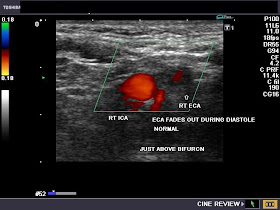

ECA and ICA - systole- color flow present:

ECA- late diastole- fades out:

ECA- no flow during late diastole: absent color flow signal

A very useful sign to identify the normal ECA is looking for flicker or fading out of the Color Doppler flow in the ECA during diastole. This is due to the very low absent flow in the ECA during diastole, as opposed to the ICA and CCA, both of which show significant flow during diastole. As a result, the ECA flickers on during cardiac systole (see Color Doppler images of the ECA and ICA above) and fades out (absent flow) during diastole). 3 of the Color Doppler images above are axial sections through the ECA and ICA while the other 3 images show the ECA and ICA just emerging from the bifurcation of the CCA (common carotid artery). All images by Joe Antony, MD. Machine used here is the Toshiba Nemio-XG ultrasound system.